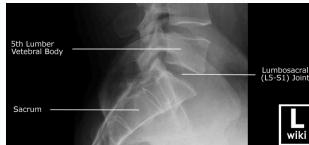

Radiographic (X-Ray) Views

- Standard Views: AP (Anteroposterior), LAT (Lateral)